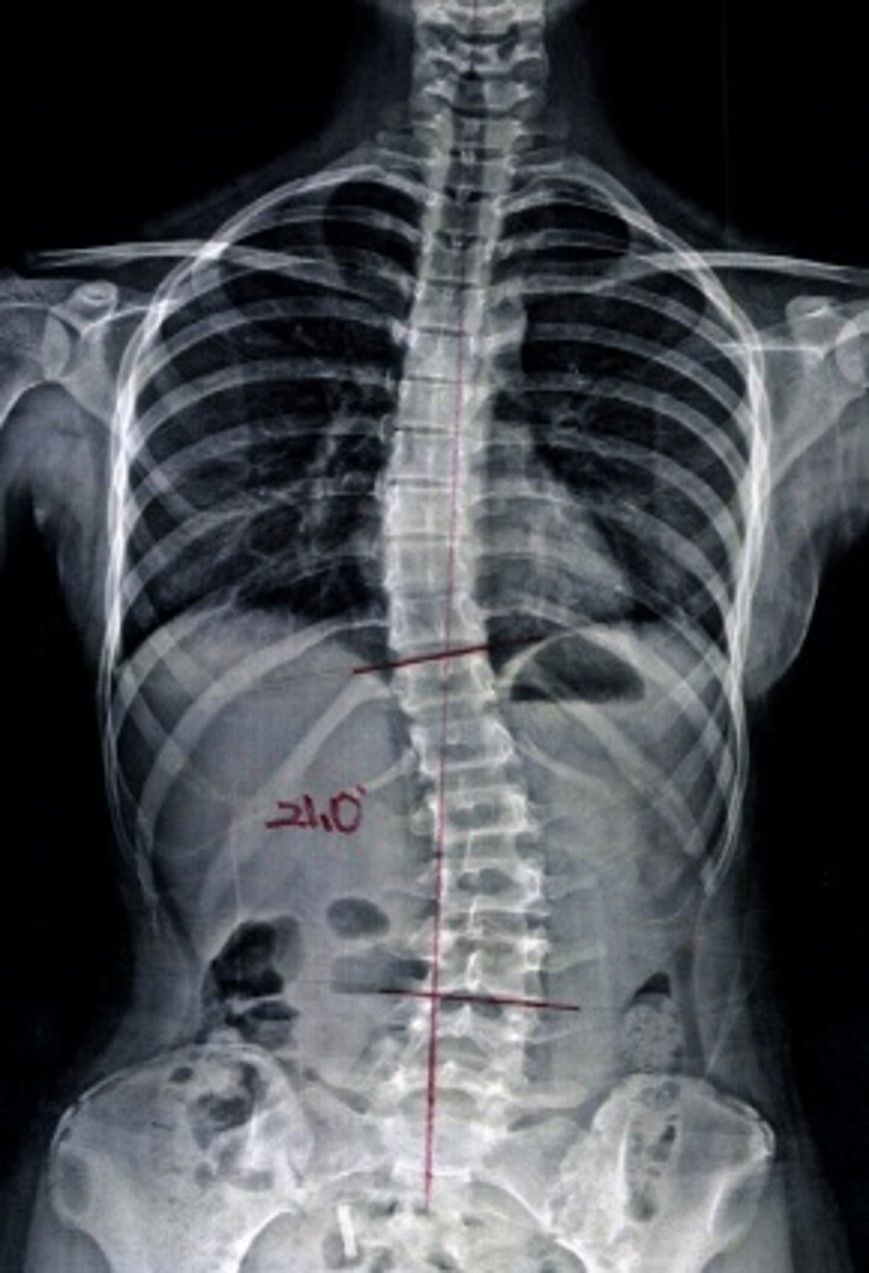

치료 전후 비교

AFTER

치료 후 척추 엑스레이

치료 후

평균 9.7° 개선

서울 대형병원 임상시험

2024-2025

• 대상자: 특발성 척추측만증 환자 24명

• 치료기간: 주 3회, 12주간 총 36회

• 결과: 100% 환자 Cobb's angle 개선